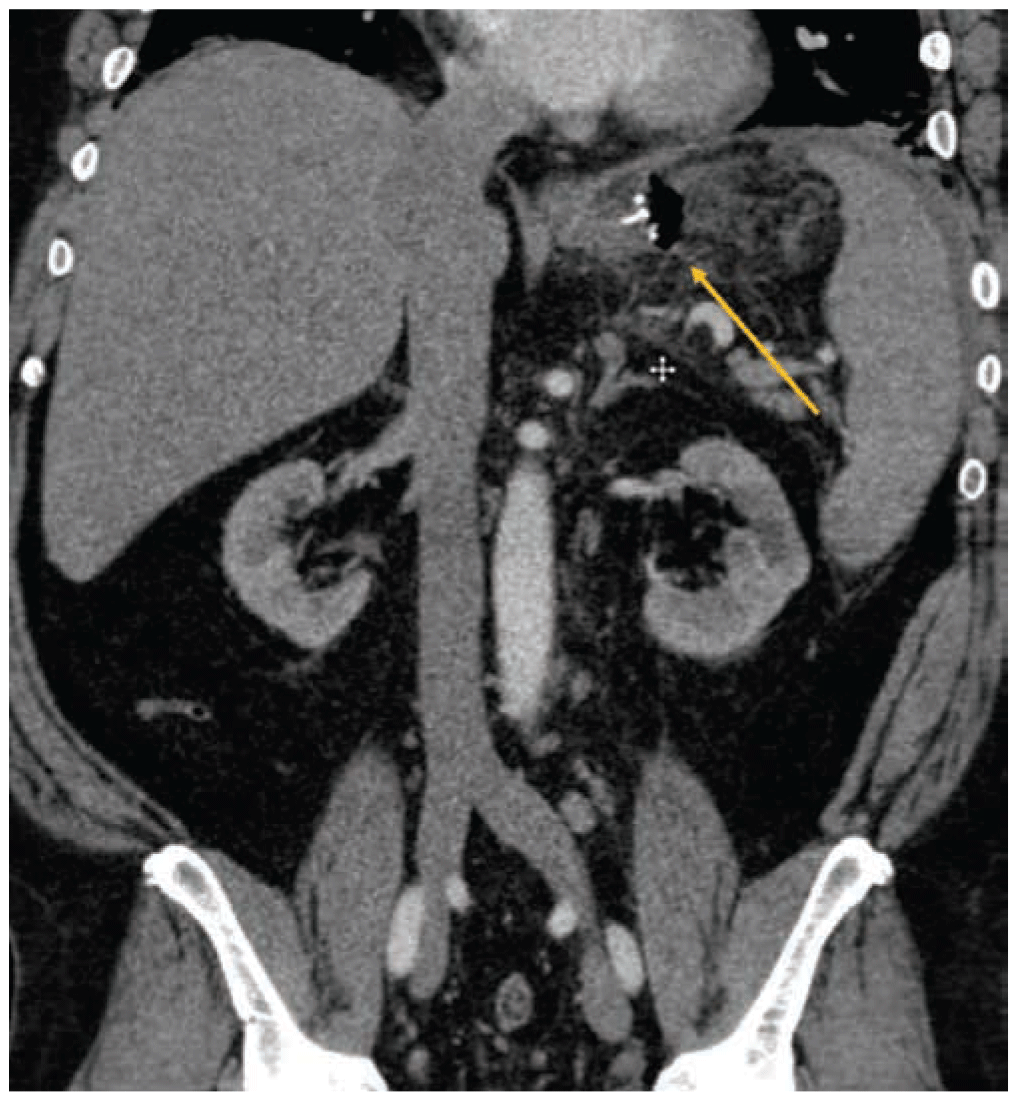

Acute appendicitis remains a therapeutic challenge during active pregnancy. Both laparascopic and open approaches can be considered; the techniques remain largely the same, with a few caveats. Fetal monitoring may be performed using a transvaginal or left lateral abdominal wall approach. For open appendectomy, ultrasonography and magnetic resonance imaging may provide direction for the incision. Laparascopic appendectomies should be approached with a open trocar placement in the midline, with direct visualization. Late-term pregnancies may require alternative approaches in the subcostal region, and the patient may be rolled with their left side down to facilitate exposure of the appendix and relieve pressure on the inferior vena cava.